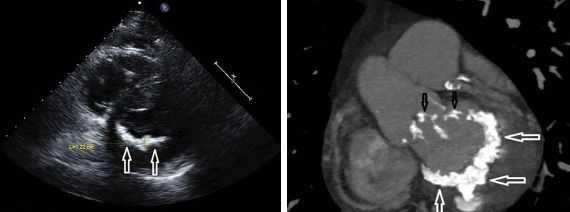

При рентгенографии грудной клетки констатируется выраженное увеличение правого предсердия, расширение ствола и ветвей ЛА и ВПВ. С помощью эхокардиографии получаются доказательные признаки трикуспидального стеноза: уменьшение размеров атриовентрикулярного отверстия, утолщение и неполное раскрытие створок, дилатация правого предсердия, изменение скорости кровотока через правое предсердно-желудочковое отверстие.